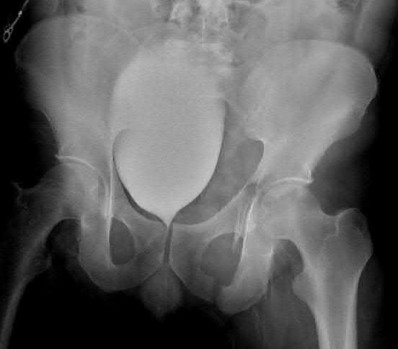

Question 11:

A poly-trauma patient presents hemodynamically unstable with an anteroposterior compression (APC-III) pelvic ring injury. A circumferential pelvic binder is requested to reduce pelvic volume and control hemorrhage. To be anatomically effective, the binder must be centered precisely over which of the following landmarks?

Correct Answer: Greater trochanters

Explanation:

For optimal mechanical advantage and effective reduction of an 'open book' pelvic fracture (APC type), a pelvic binder must be applied directly over the greater trochanters of the femurs. Applying it higher, such as over the iliac crests, is a common error that fails to adequately close the pelvic ring and can paradoxically open the true pelvis.